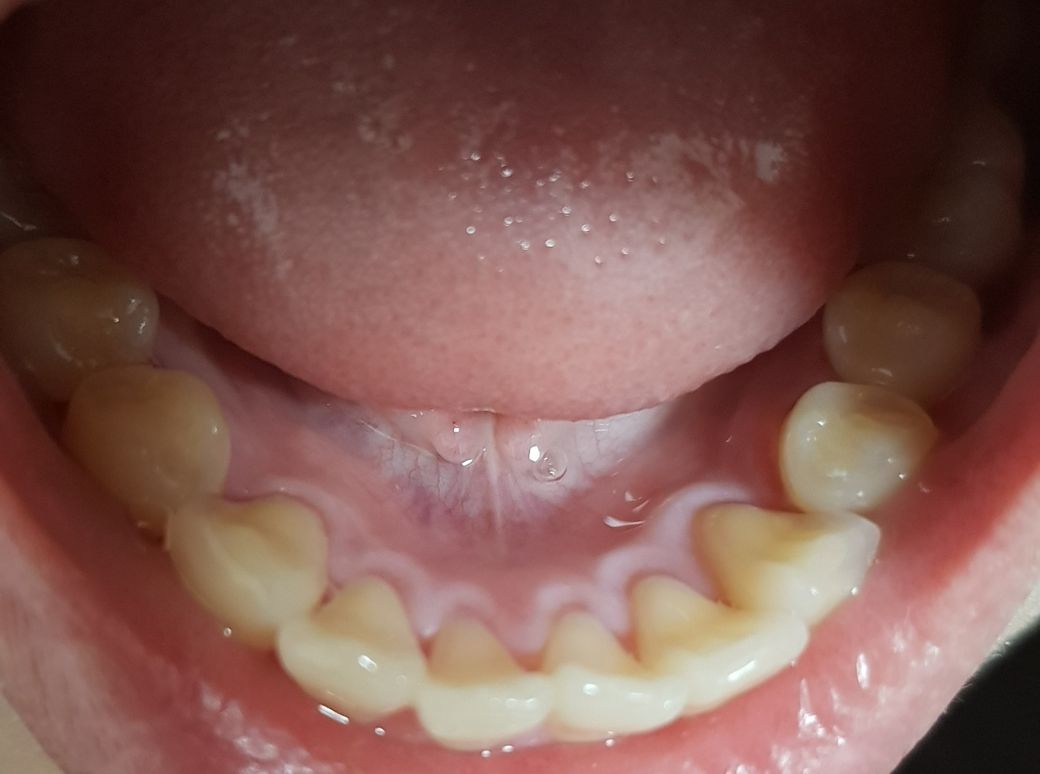

10월 31일에 스케일링을 받았는데 그 이후로 앞쪽 아랫니 부분 잇몸

이 가렵습니다.

특히 잇몸 안쪽이 하얗게 부은 것 같아요.

• 1번 째 사진

스케일링 이전에 치석이 많았다면 2주 정도는 불편감이나 이질통 등이 나타날 수 있습니다. 현재 사진으로는 큰 문제가 되지 않아 보이며 조금 더 증상을 지켜보시길 바랍니다.

스케일링을 하고 잇몸이 하얗게 되는 것은 염증이 줄어들고 있다는 것입니다.

스케일링 후에 일시적으로 시린느낌이나 잇몸에 통증을 느낄수는 있지만 곧 회복되는 현상이기에 걱정하지 않으셔도 됩니다. 현재사진상으로 크게 문제가 되어 보이지는 않으며, 만약 불편감이 지속시에는 치과 진료를 받길 권합니다.